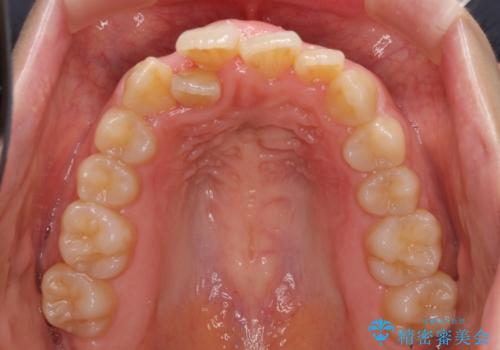

- 右上の八重歯と、左下八重歯を抜いてしまったことを気にして来院された患者様です。

下顎は既に犬歯を1本抜歯しているため、上顎右側第一小臼歯を抜歯し、ワイヤー装置にて歯列を整えることとしました。

変則的な抜歯となるため、正中と人中がずれる可能性がありましたが、仕上がりは上下正中を揃えることができました。